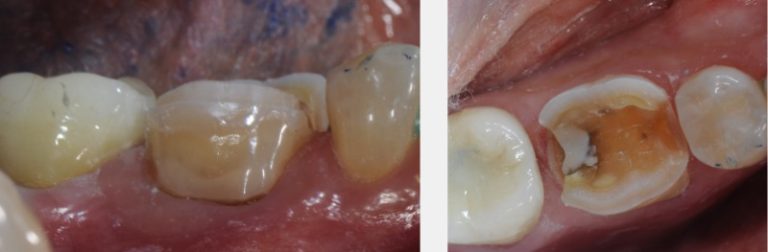

Caries detection dyes help dentists determine when to stop tooth preparations in conservative treatment.